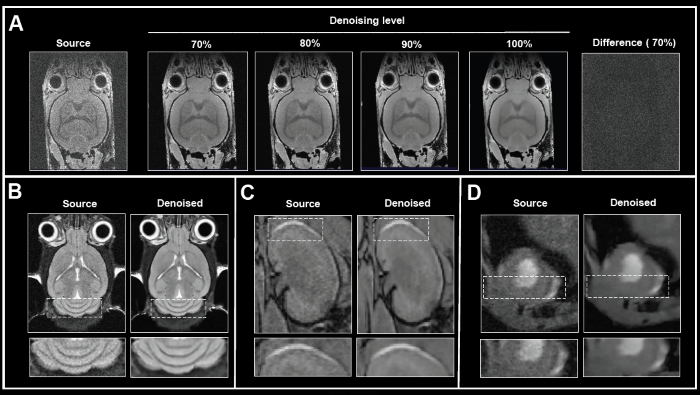

Beyond the choice of network, choosing a denoising level is also possible. Fig. 2A shows the effect of applying different denoising levels for reconstructing images. Mouse brain data was obtained ex vivo, and the original data was reconstructed without denoising and while heightening denoising levels (70-100%).

Increasing denoising levels progressively removed noise from images. No artifacts were introduced throughout the procedure. Computing a difference image between the source and 70% denoised images showed that noise alone was selectively removed.

If the original signal at the image edges is lower due to factors such as bandwidth selection or high denoising levels (i.e., 90 and 100%), the edges can appear blurry. Thus, the ideal denoising level, producing a trade-off between efficient noise removal and edge blurring, should be established individually for each dataset or for each application protocol at a minimum.

Figure 2. The effect of image denoising on image quality. A) Applying increasing levels of denoising. Shown are axial images of a 3D T1-weighted FLASH ex vivo data of a fixed mouse head acquired at 9.4 Tesla without (Source) and different levels (70-100%) of denoising. A difference image between the source and 70% denoised images was computed. B)-D) Comparison of in vivo images reconstructed with no denoising and with 70% denoising. B) Coronal T2-weighted TurboRARE images of a mouse brain acquired at 3 Tesla. C) Coronal 3D FISP images of mouse kidney acquired at 7 Tesla. D) Short axis view of a mouse heart acquired with a flow-compensated triggered FLASH sequence at 9.4 Tesla. For different data, either no denoising (Source) or denoising using individual networks and a pre-denoising of 50% was applied (Denoised). Image Credit: Bruker BioSpin Group

The usefulness of Smart Noise Reduction was shown in-vivo mouse data of different organs obtained at various magnetic field strengths (Fig. 2B-D). Compared to the reference images of the brain, kidney, and heart, reconstruction with 70% denoising provided images with considerably less noise and improved appearance of anatomical details and edges.